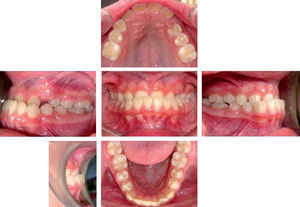

In the finishing phase, up and down intermaxillary elastics with class I vector were used removing the appliances definitively at the end of two years and seven months of intermittent treatment, with class I molar and canine occlusion and a straight profile.

OBTAINED RESULTSWe obtained a good projection of the lower facial third, a lower and upper lip with better dentoalveolar support, a pleasant smile, straight profile, facial harmony and lips in the same plane, molar and canine class I, adequate overbite and overjet lines and centered midlines (Figure 7), with no radical changes in the cephalometric measurements (Figure 8andtable II).